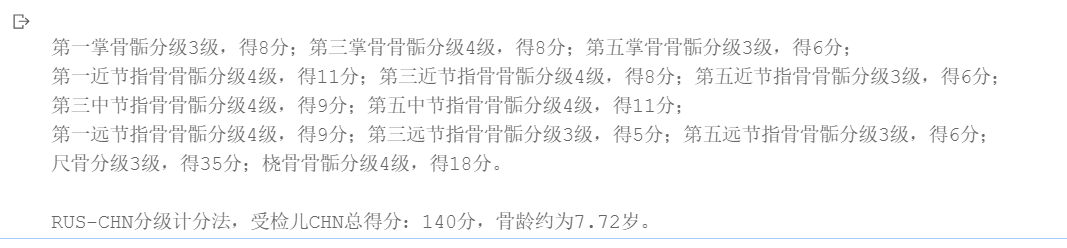

第一掌骨骺分级3级,得8分;第三掌骨骨骺分级4级,得8分;第五掌骨骨骺分级3级,得6分;

第一近节指骨骨骺分级4级,得11分;第三近节指骨骨骺分级4级,得8分;第五近节指骨骨骺分级3级,得6分;

第三中节指骨骨骺分级4级,得9分;第五中节指骨骨骺分级4级,得11分;

第一远节指骨骨骺分级4级,得9分;第三远节指骨骨骺分级3级,得5分;第五远节指骨骨骺分级3级,得6分;

尺骨分级3级,得35分;桡骨骨骺分级4级,得18分。

RUS-CHN分级计分法,受检儿CHN总得分:140分,骨龄约为7.72岁。